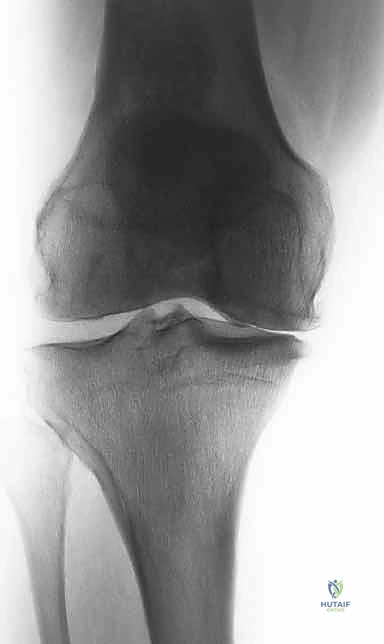

لفهم أهمية عملية (HTO)، يجب أولاً فهم كيف تعمل الركبة. مفصل الركبة يتحمل وزن الجسم بالكامل تقريباً أثناء المشي والوقوف. ينقسم المفصل إلى ثلاث حجرات رئيسية: الحجرة الداخلية (الإنسية)، الحجرة الخارجية (الوحشية)، وحجرة الرضفة (الصابونة).

في الحالة الطبيعية الميكانيكية، يمر "محور تحمل الوزن" (Weight-bearing axis) مباشرة عبر منتصف الركبة، مما يوزع الضغط بالتساوي. ولكن، عند حدوث تقوس في الساقين (Varus Deformity)، ينزاح هذا المحور إلى الداخل، مما يضع ضغطاً هائلاً ومدمراً على الغضروف الداخلي للركبة.

هذا الضغط المستمر يؤدي إلى تآكل الغضروف بشكل أسرع من الطبيعي، مما يسبب احتكاك العظم بالعظم، وهو ما يُعرف بخشونة الركبة. هنا يأتي دور الجراحة لإعادة توجيه هذا المحور نحو الجزء الخارجي السليم من الركبة.

تُعد الأشعة السينية (X-rays) الممتدة من الحوض إلى الكاحل (Scanogram) ضرورية جداً لحساب زاوية التقوس بدقة وتحديد مقدار التعديل المطلوب جراحياً.